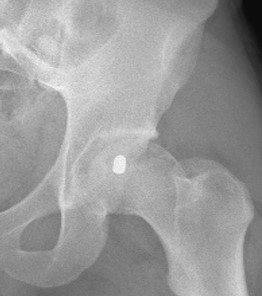

Retained bullet in the left femoral head

Retained bullet in the left femoral head removed with surgical dislocation and bone and cartilage grafting.